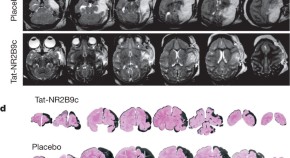

• Tat-NR2B9c, a PSD-95 inhibitor, is shown to reduce stroke-induced behavioural and neuroanatomical deficits in cynomolgous macaques when administered in the presence of an ischemic penumbra, suggesting the potential of PSD-95 inhibition as a neuroprotectant strategy for clinical investigation.

Volume: 483, P: 213-217